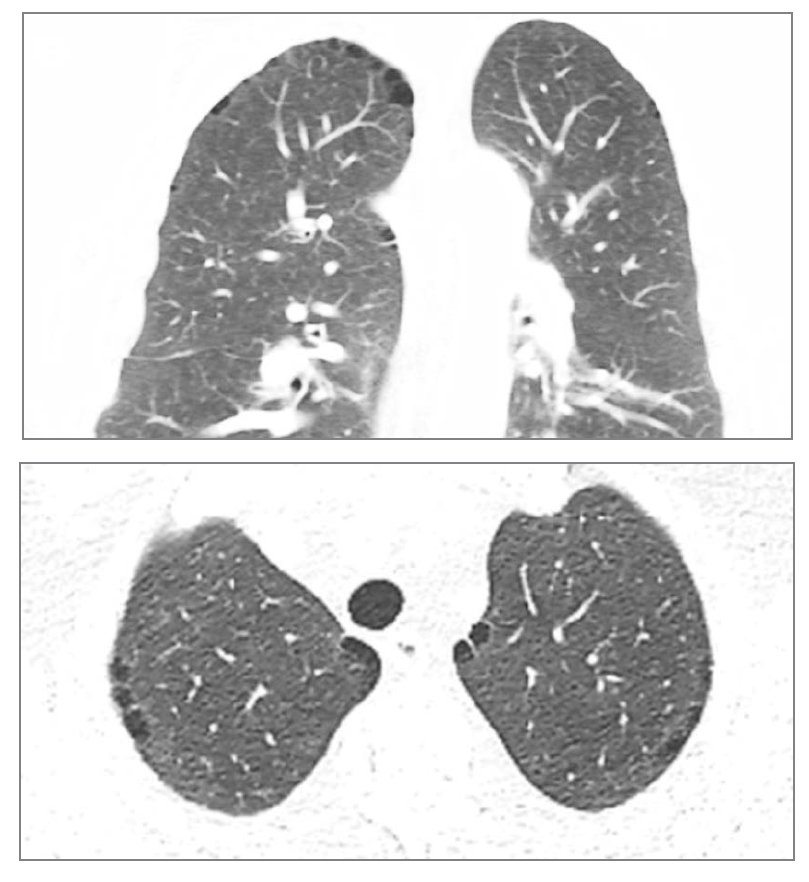

What feature is seen at the top? What condition would this be?

Blebs. Centrilobular emphysema.

What is this?

Panlobular emphysema